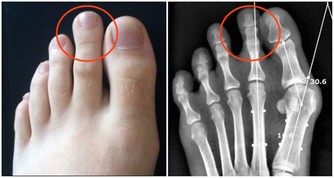

三、肺臟排毒

肺是最容易積存毒素的器官之一。因為人每天的呼吸會將約1000升空氣送入肺中,空氣中飄浮的許多細菌、病毒、粉塵等有害物質也隨之進入肺臟。當然,肺也能通過呼氣排出體內代謝的二氧化碳等廢氣和其他有害入侵者。

肺臟有毒素堆積,會使人經常感冒、咳嗽、哮喘,氣管敏感。中醫認為,肺臟和大腸是一套系統,互為表里。當肺臟有毒素時,腸道內也會有不正常淤積,出現便秘。

肺排毒的時間是凌晨3點到5點。肺臟功能最強的時間是早上7點到9點,此時最好能夠通過運動排毒。在肺功能最強的時候進行慢跑等有氧運動,能強健肺排出毒素的功能。